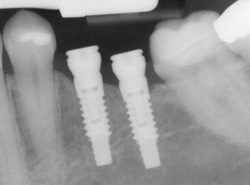

An implant is a synthetic tooth root in the shape of a post that is surgically placed into the jawbone. The “root” is usually made of titanium: the same material used in many replacement hips and knees, and a metal well suited to pairing with human bone.

Single or Multiple Implants

Implants are extremely versatile. If you are missing only one tooth, one implant plus one replacement tooth will do the trick. If you are missing several teeth in a row, a few strategically placed implants can support a permanent bridge (a set of replacement teeth).